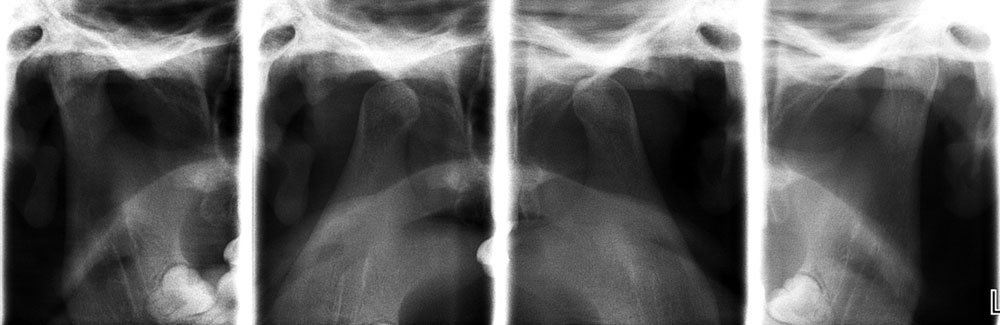

Raio X da articulação temporomandibular (ATM), é uma das radiografias extrabucais e geralmente é solicitadas para a analise dos contornos anatômicos (cabeça da mandíbula, eminência articular, fossa mandibular) e dinâmica articular (posicionamento das cabeças da mandíbula com relação à fossa mandibular e eminência articular).

São realizada duas radiografias para a analise da ATM, uma é com a boca fechada e a outra com a boca aberta o máximo que o paciente puder, ajuda a avaliar o grau de movimentação e a relação com as estruturas vizinhas.